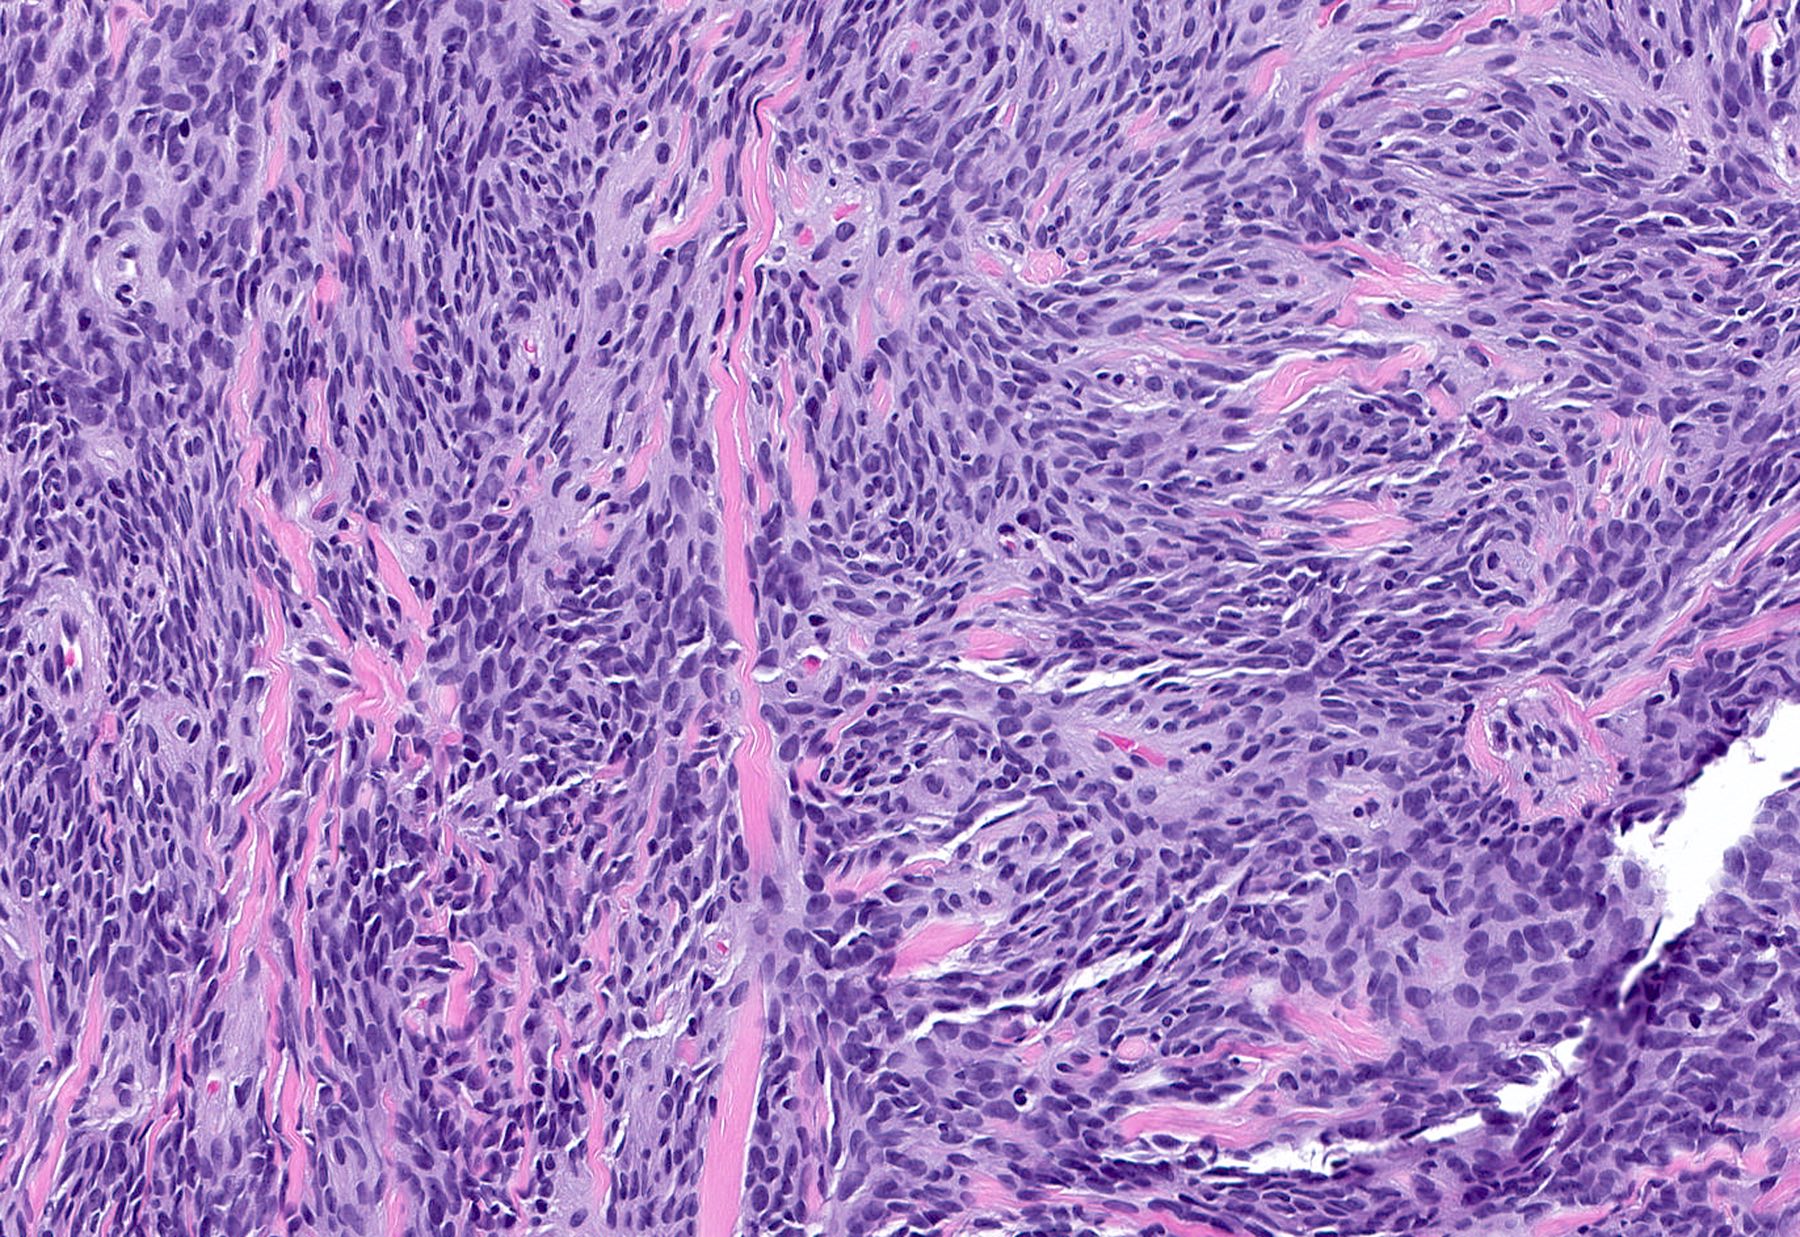

Microscopic (histologic) description

- Well circumscribed, lacks true capsule, rarely infiltrative

- Bland, uniform, short to elongated spindle cells arranged as short haphazard intersecting fascicles admixed with bands of hyalinized, brightly eosinophilic collagen and variable amounts of fat

- No more than mild nuclear atypia

- Mitoses usually absent, atypical mitoses and necrosis absent

- Mast cells common, perivascular lymphocytic infiltrates on occasion

- Focal myxoid stromal changes common

- May show smooth muscle leiomyomatous differentiation (elongated spindle cells with cigar shaped nuclei and pink cytoplasm)

- Variants:

- Cellular: dense proliferation of myofibroblasts, ratio of spindle cells to collagen increased compared with classical variant, may have infiltrative borders, storiform or herringbone arrangement

Microscopic (histologic) images